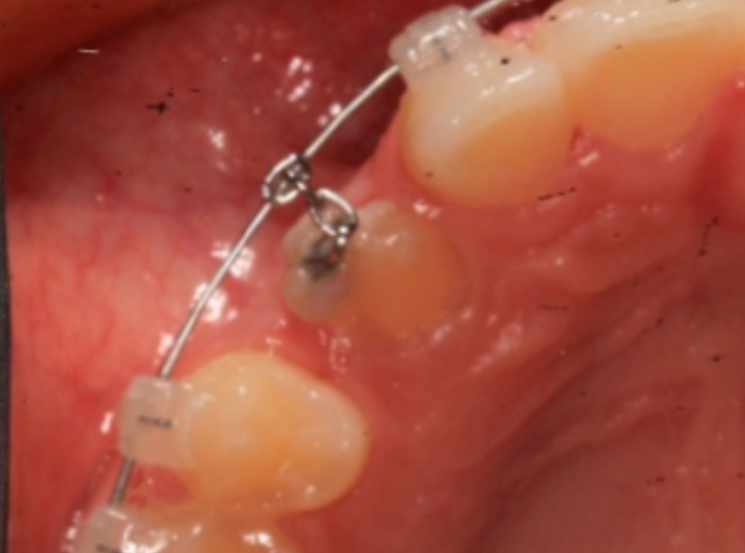

Step 2: Surgical Exposure and Bonding

An oral surgeon performs a procedure called an expose and bond.

During this procedure:

The surgeon gently uncovers the impacted tooth

A small orthodontic attachment is bonded to the tooth

A small chain or bracket is attached so the orthodontist can guide the tooth into position

This is a common and routine procedure used to help bring impacted teeth into the smile.

Step 3: Orthodontic Movement of the Tooth

After the attachment is placed, orthodontic appliances such as braces or clear aligners are used to slowly guide the canine into its proper position.